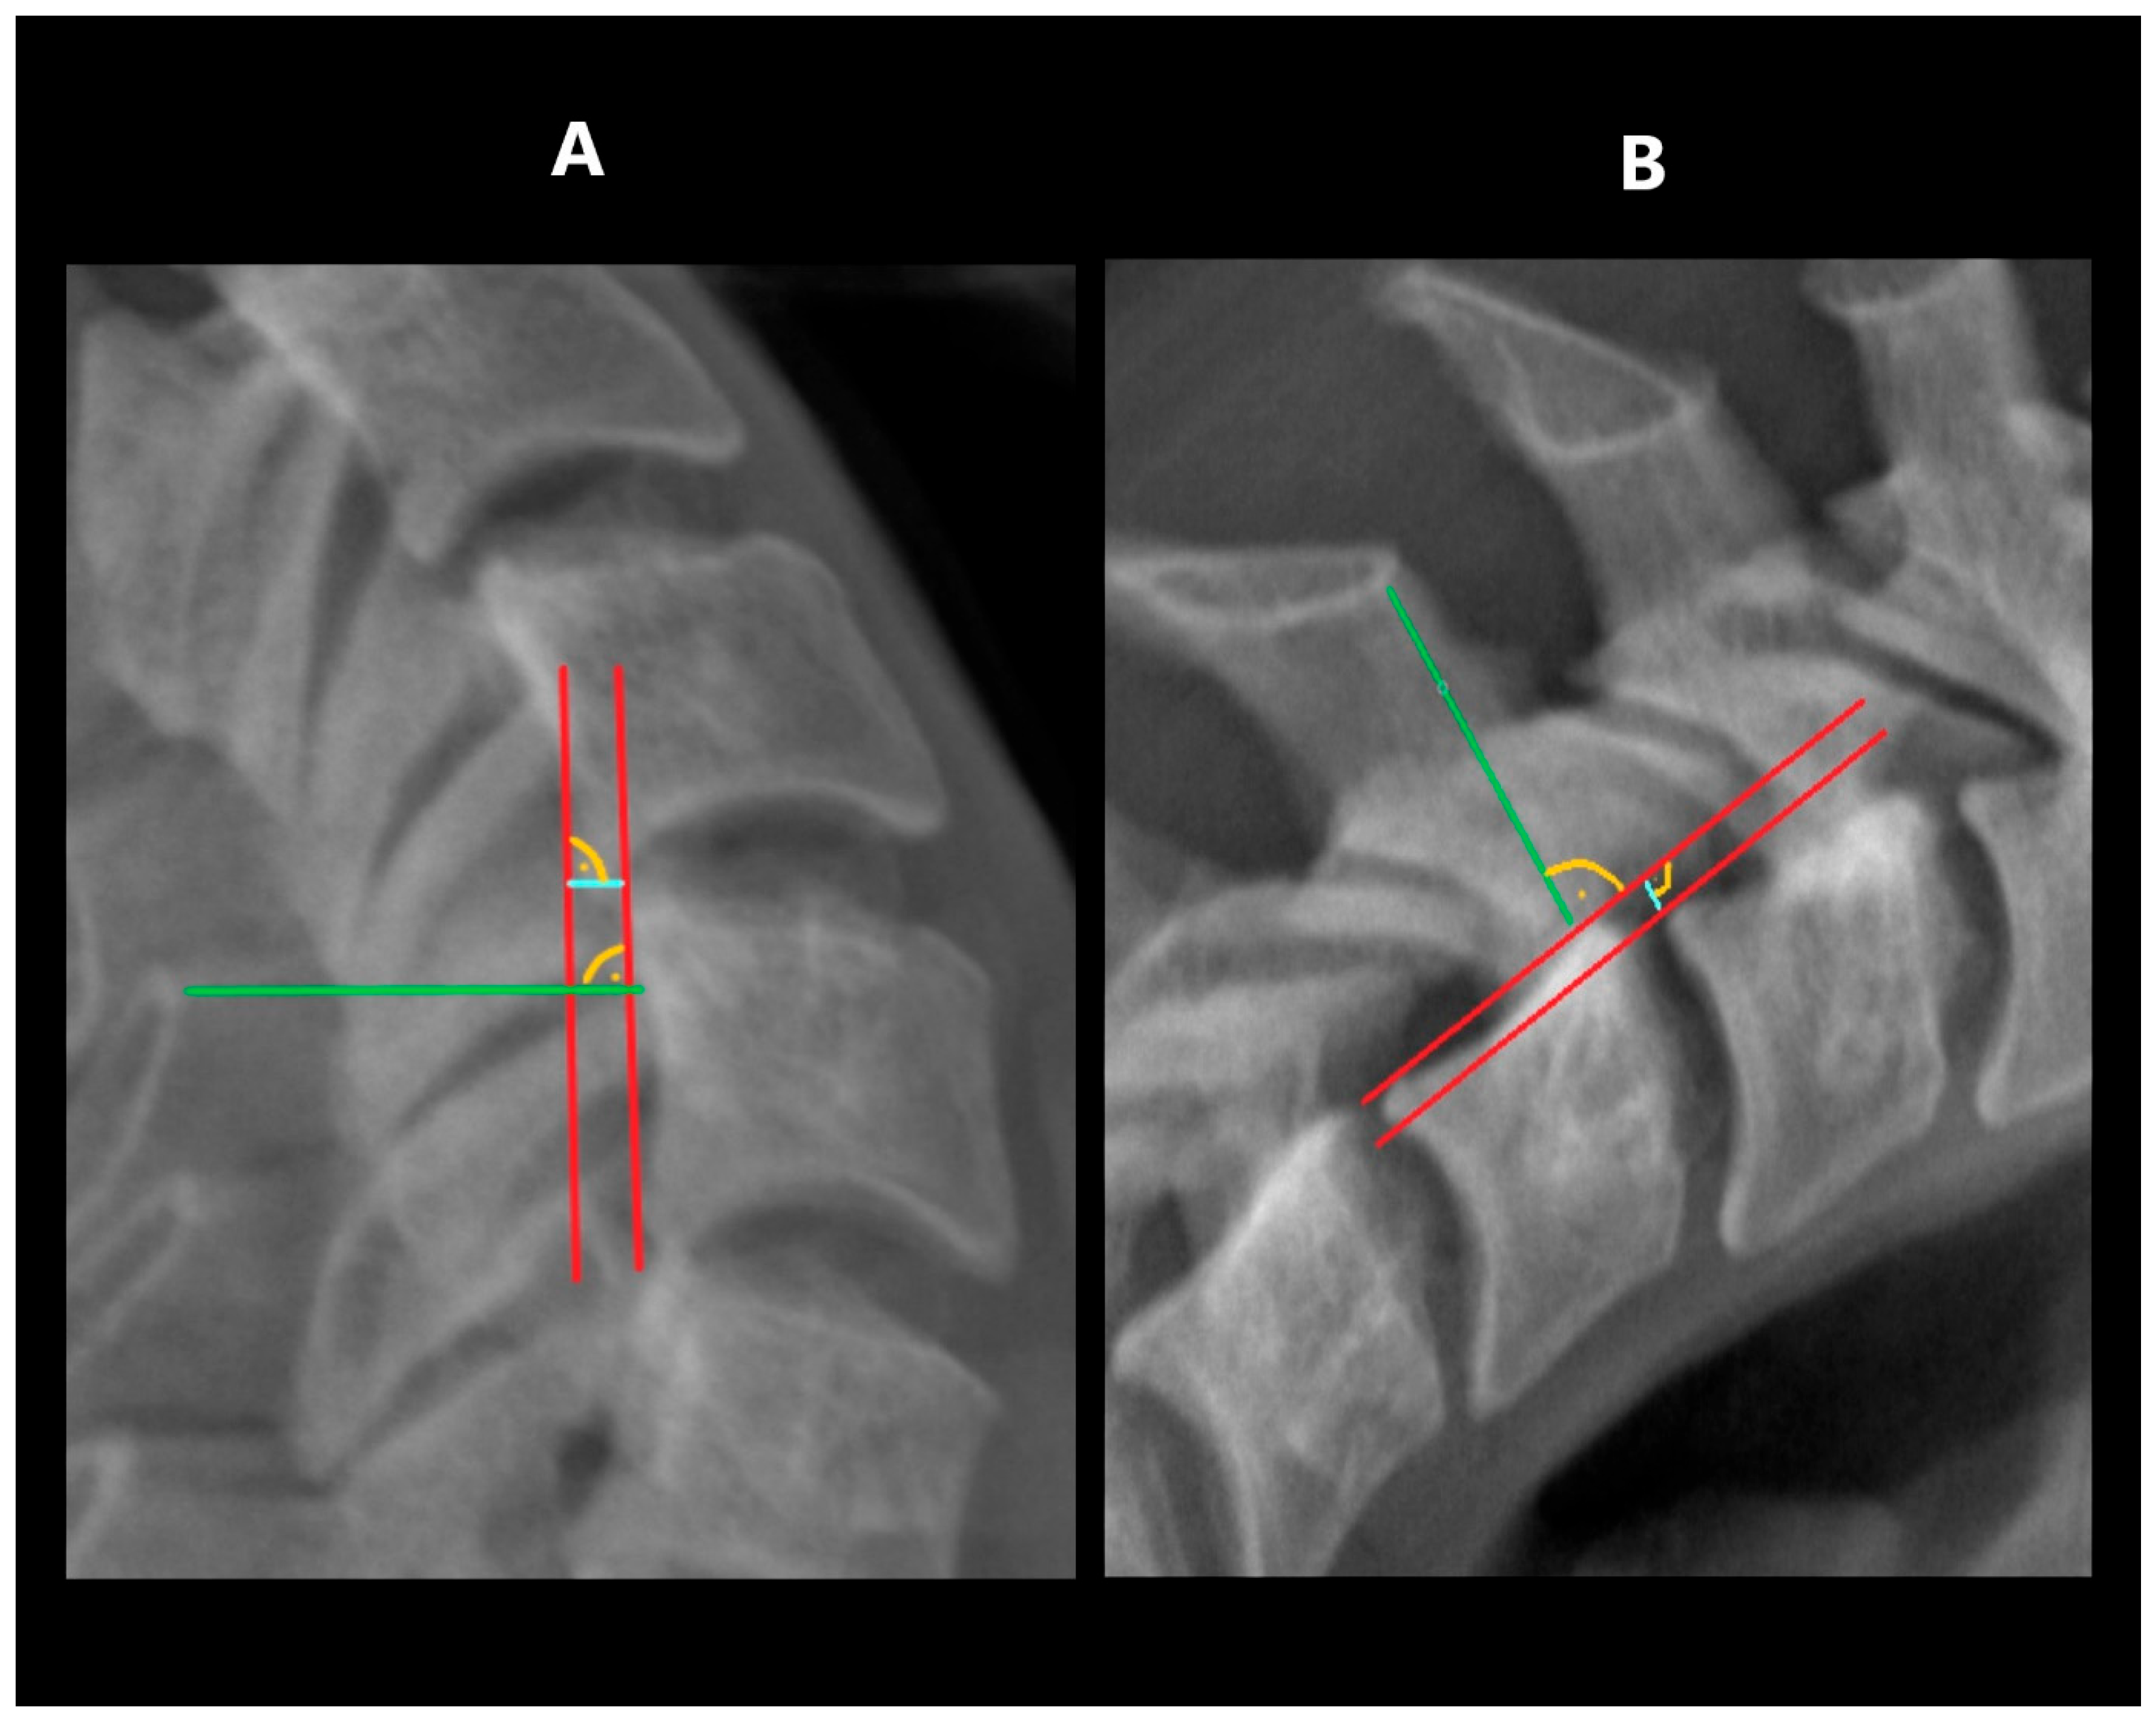

The range of angular motion was measured in the flexion and extension projections. The measurement was performed by determining the tangent to the lower contour of the upper vertebra and a second tangent drawn to the upper contour of the lower vertebra (Figure 3). The sum of the angles obtained in flexion and extension at a specific level was defined as its segmental angular mobility.

This study also determined the overall ROM of the C2–C7 cervical spine by summing the segmental angular mobility values for each level.

Figure 3. Measuring ROM: (A)—in extension, (B)—in flexion.